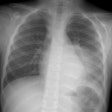

X-ray:

The lesion typically presents with a pleural effusion with associated smooth, nodular pleural thickening (resembling a mesothelioma).